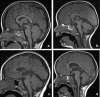

Background and purpose: The splenium of the corpus callosum is the most posterior part of the corpus callosum. Its embryological development, anatomy, vascularization, function, imaging of pathology, possible pathophysiological mechanisms by which pathology may develop and the clinical consequences are discussed.

Methods: A literature-based description is provided on development, anatomy and function. MR and CT images are used to demonstrate pathology. The majority of pathology, known to affect the splenium, and the clinical effects are described in three subsections: (A) limited to the splenium, with elaboration on pathophysiology of reversible splenial lesions, (B) pathology in the cerebral white matter extending into or deriving from the splenium, with special emphasis on tumors, and (C) splenial involvement in generalized conditions affecting the entire brain, with a hypothesis for pathophysiological mechanisms for the different diseases.

Results: The development of the splenium is preceded by the formation of the hippocampal commissure. It is bordered by the falx and the tentorium and is perfused by the anterior and posterior circulation. It contains different caliber axonal fibers and the most compact area of callosal glial cells. These findings may explain the affinity of specific forms of pathology for this region. The fibers interconnect the temporal and occipital regions of both hemispheres reciprocally and are important in language, visuospatial information transfer and behavior. Acquired pathology may lead to changes in consciousness.